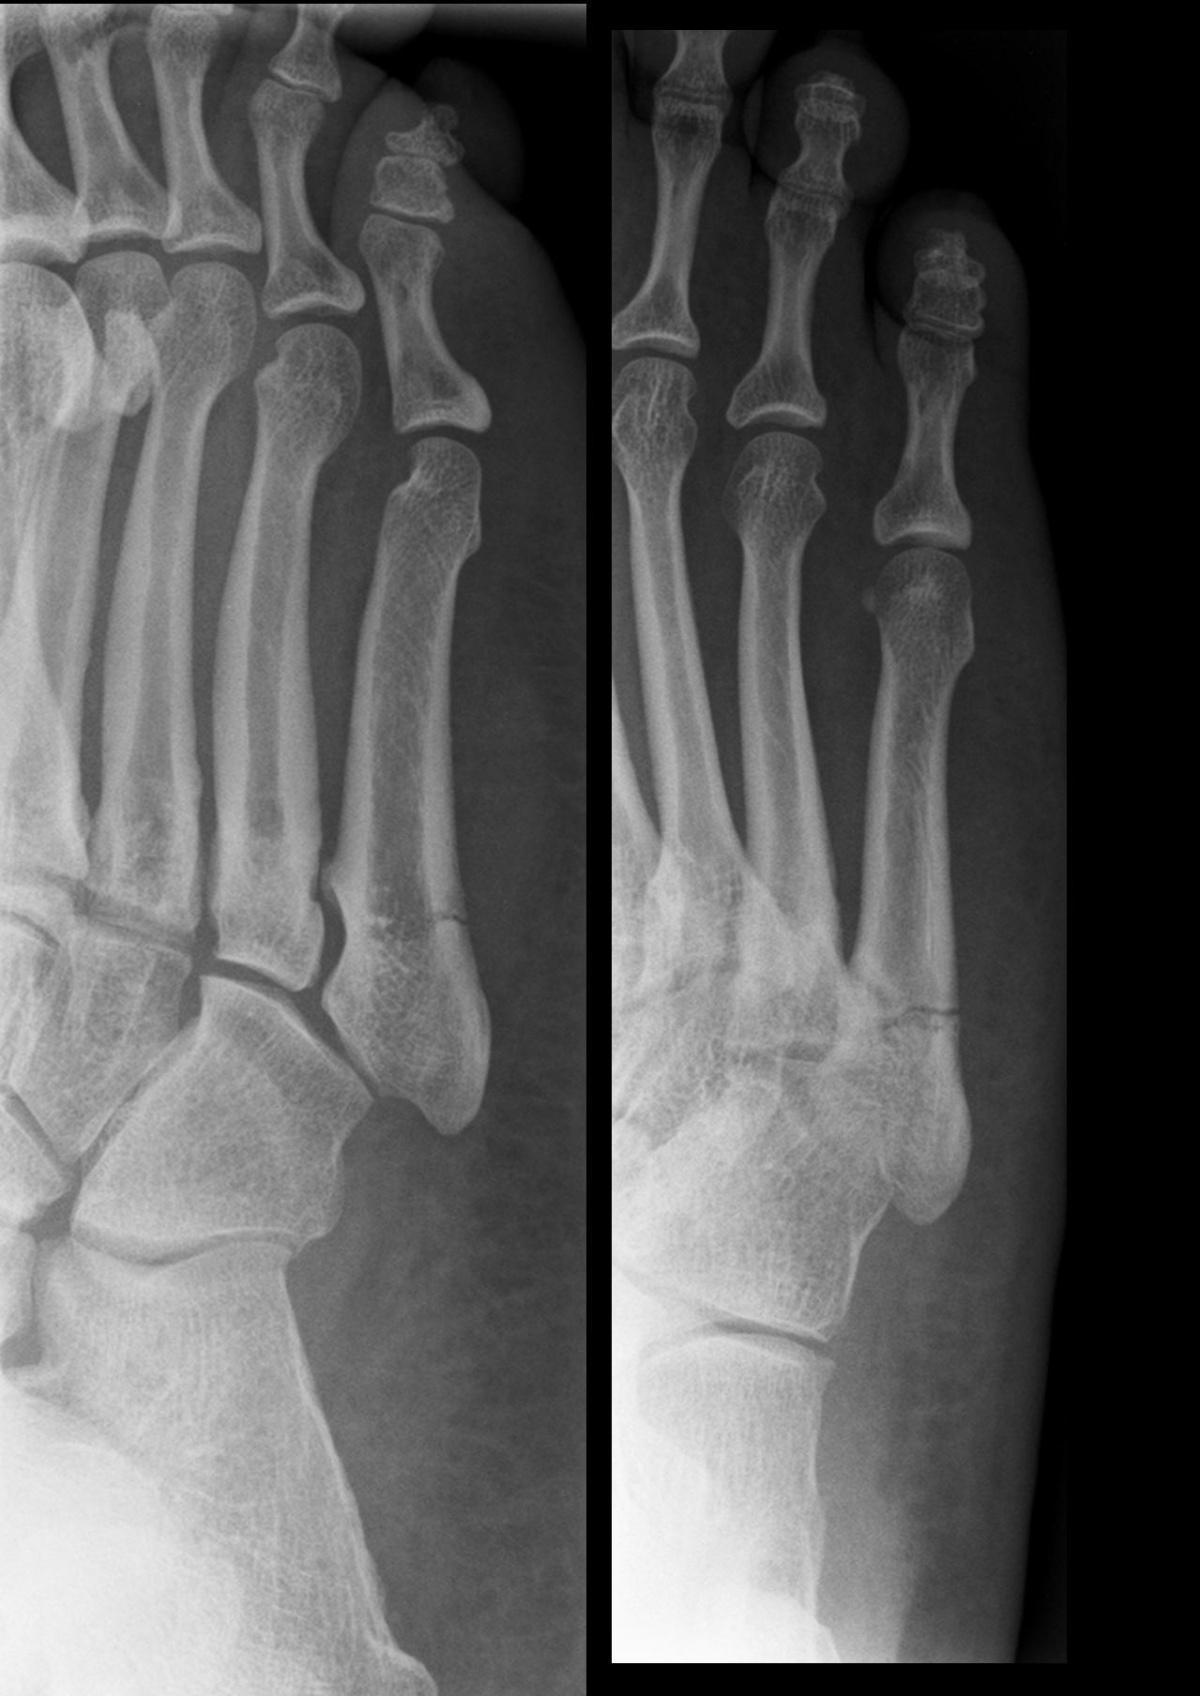

Fracture de metatarsien

Lucien Monfils - Own work, CC BY-SA 3.0, Link